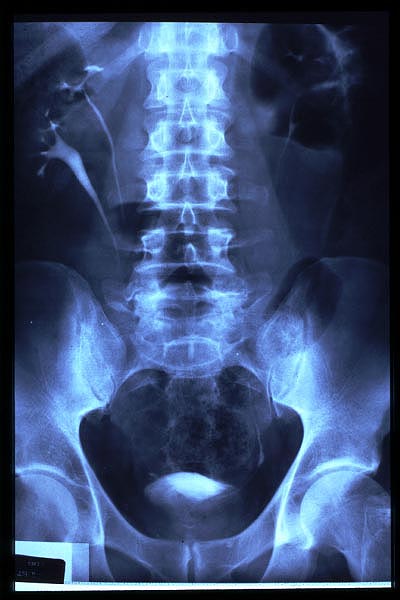

E de Paget